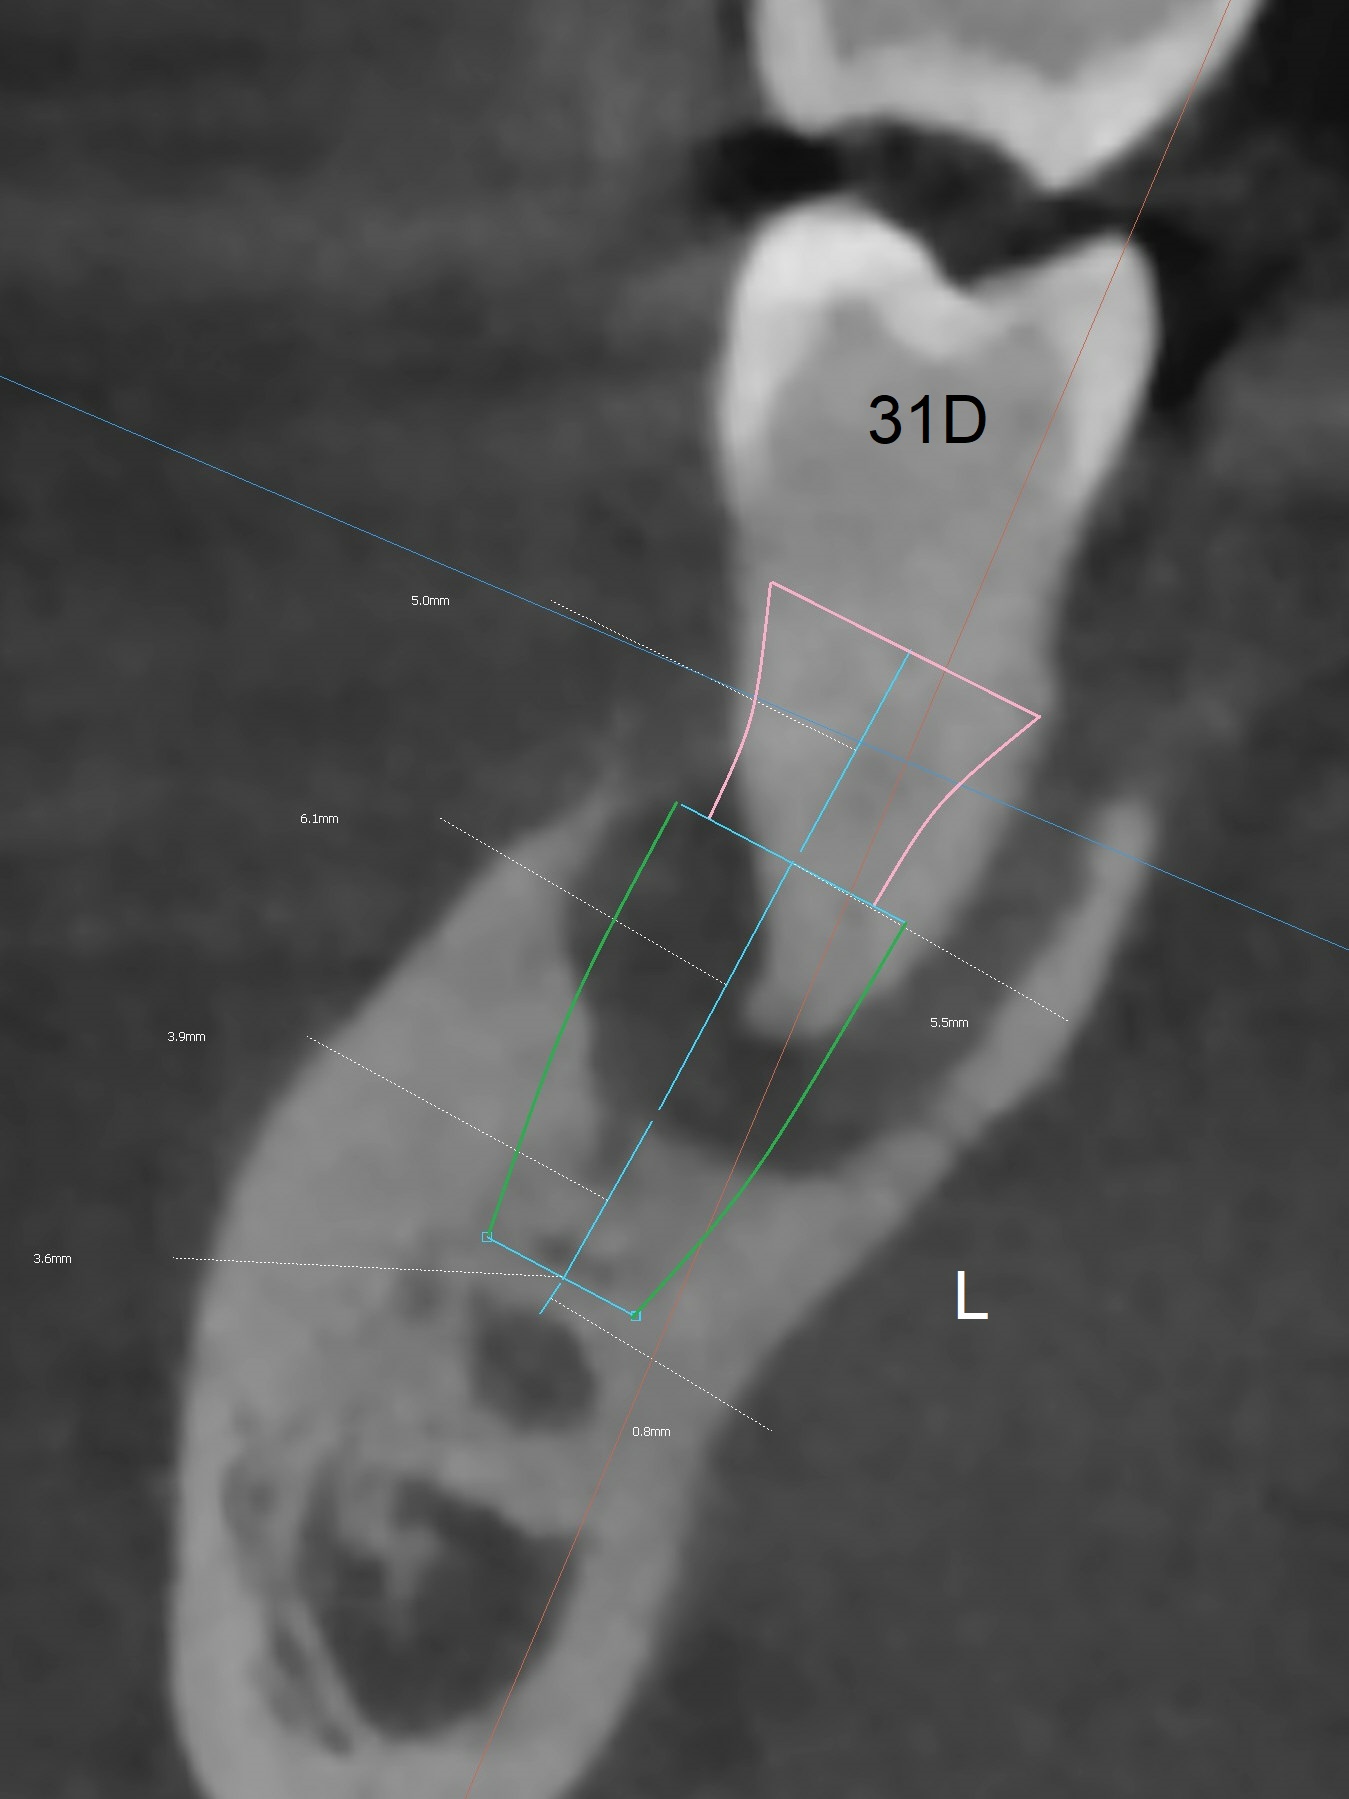

Extraction of the mobile tooth #31 (Fig.1) and debridement of the large socket are not difficult. But making osteotomy buccally does not seem to be easy. It will be difficult to restore. Instead, socket preservation is accomplished by filling the socket with approximately 1.5 cc of Mineralized Cortical/Cancellous allograft until the crest (Fig.2,5). The socket opening is closed by insertion of 4 pieces of PRF membranes (Fig.3) and 4-0 Chromic gut sutures (Fig.4). In the end of surgery, it appears that osteotomy in the center of the socket could be a better approach. Postop re-analysis of CT (Fig.6) and PA (Fig.7) shows that there is 3.9 mm of the native bone to support a 5.5x10 mm implant. Sinus Lift Master Kit should be used with 2 mm initial drill and 2.8 and 3.6 mm round drills with 4 mm stopper.